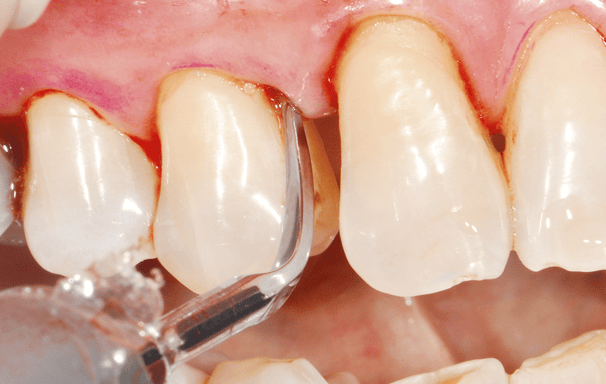

Destartraje supragingival

Consiste en eliminar el sarro y la placa que se acumulan sobre la línea de las encías. Se realiza con instrumentos manuales o ultrasonido para prevenir enfermedades periodontales.

Destartraje subgingival

Se enfoca en la limpieza de debajo de la línea de las encías para eliminar el sarro y la placa que no se puede ver a simple vista. Esto ayuda a reducir la inflamación y la infección de las encías.